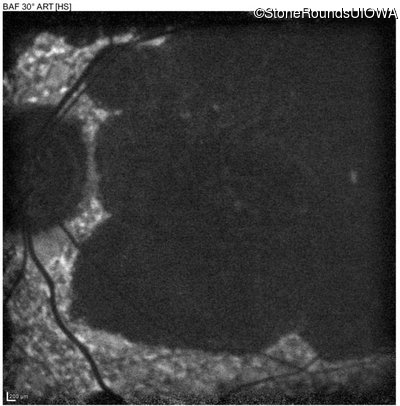

| AR Stargardt Disease | ABCA4 | Cys205Phe TGC>TTC | Gly863Ala (G)GA>(G)CA | AR |